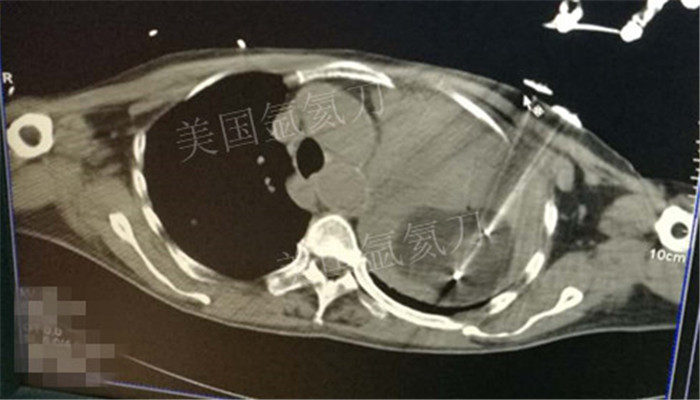

下一篇:氩氦冷冻治疗最大径8.2肿瘤,冰球最大径7.9